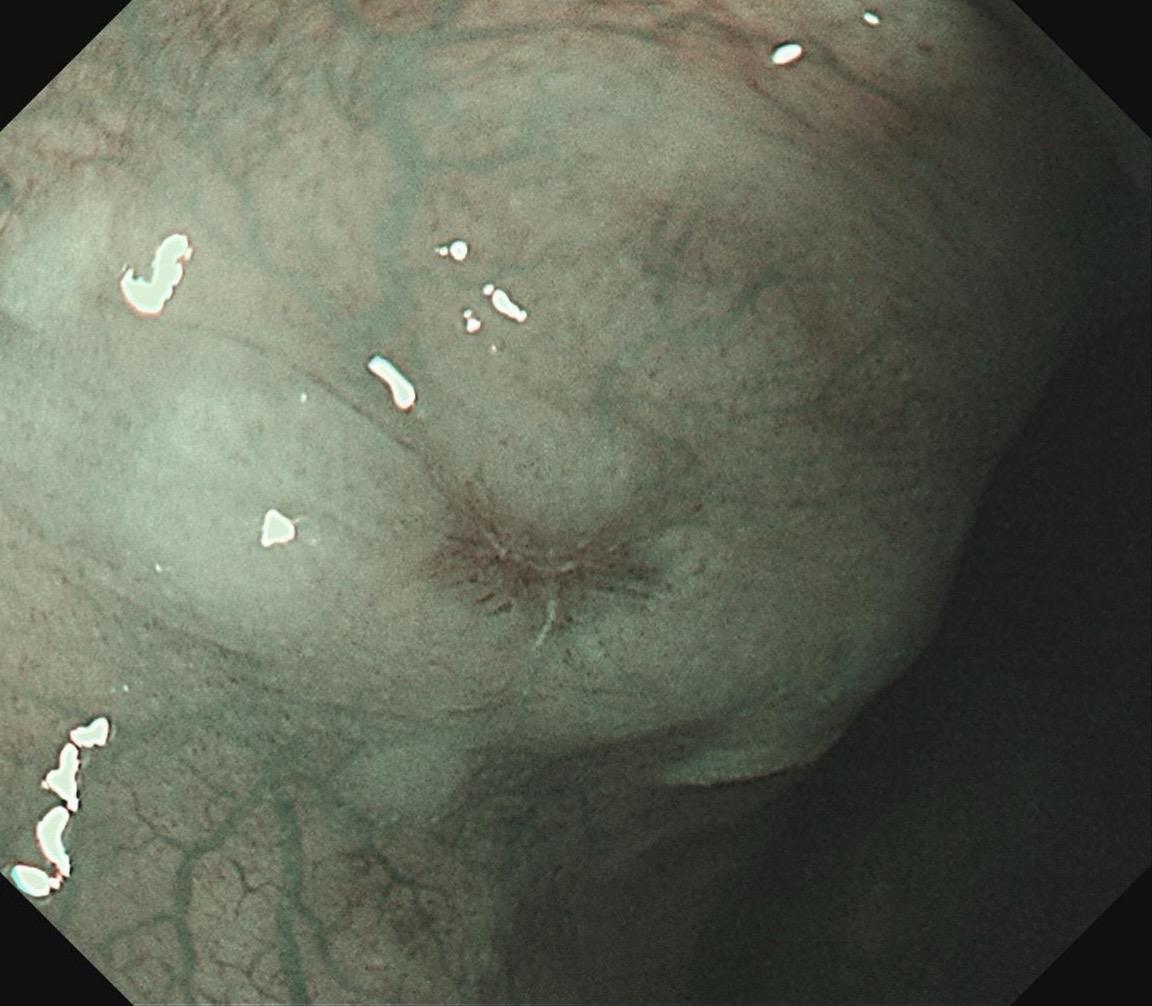

女,73岁,食管双发病变。泰州人,入院系统体检,首次胃镜检查,上段16-19cm见长条状病变,肛侧碘染局部不染;25cm处见一2mm粗糙潮红黏膜,浅凹陷,放大疑似R型不规则血管,卷发样改变,淡染,均行ESD切除。